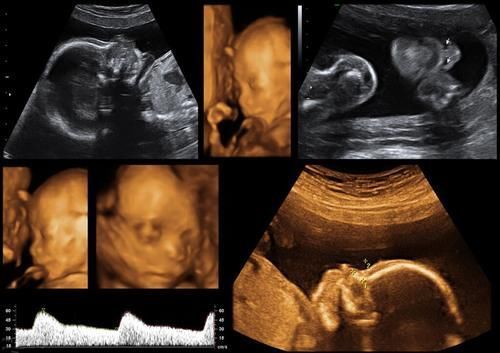

四维排畸检查

四维排畸这项检查,通常到孕中期,医生都会建议做去做,一旦孩子身上有残缺畸形,就可以提前知道。

可是很多人却认为,所谓的四维排畸和B超没有太大的区别,所以,就觉得四维排畸检查是浪费钱,很没有必要去做。

殊不知,就因为自己的无知,结果害惨了娃,让孩子一出生就被别人“贴标签”。为了让娃将来少受罪,孕期这项检查不能落下。